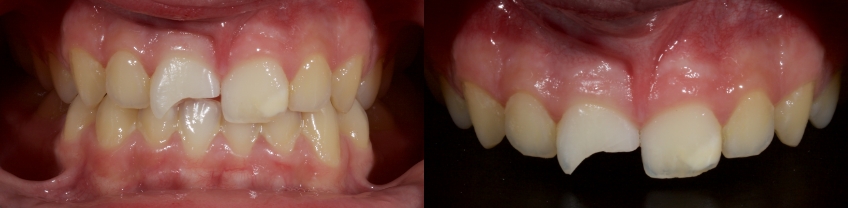

Case #1: Fragment Reattachment

Any biofilm and aprismatic enamel were removed from the tooth, and the fragment was fragmented with light hydro abrasion with 29-micron alumina at 2-3 bar pressure. The tooth and the fragment were etched with 37% phosphoric acid (Ultradent), and a fourth-generation dentin bonding agent (Kerr, OptiBond FL) was applied (the adhesive component was not light-cured).

The fragment was luted to the tooth with heated chromatic enamel shade composite (GC G-aenial A2 shade). The heater used was a Calset Warmer from Addent. The excess composite was cleaned with an interproximal carver from American Eagle and smoothed with a number three brush and modeling resin (Brush & Sculpt from Cosmedent).

The composite was heated because it gained lower viscosity to improve adaptation. Plus, heating increases the conversion of monomer to polymer, which improves the physical characteristics of the resin, such as flexural strength and wear resistance, according to research by Da Costa, Hilton, and Swift in 2011.

The resin was polymerized, and the oxygen-inhibited layer was removed by polymerization under glycerine.

The enamel fracture on 2.1 was untouched and will be managed in conjunction with esthetic management of the white hypo calcification at a later time.